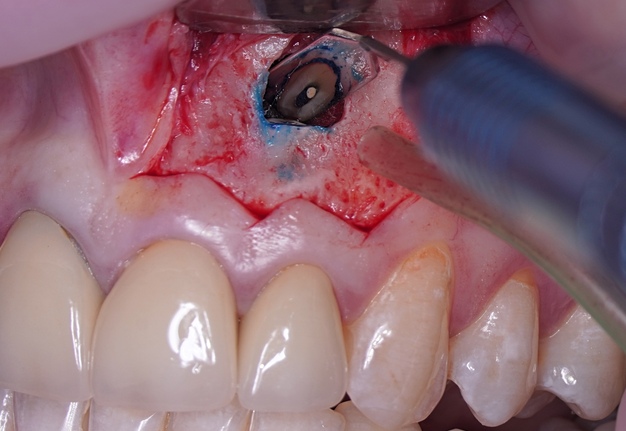

Sometimes the frenulum of the upper lip is massive and for avoid its dissection, it is permissible to perform a submarginal flap with one vertical incision located more distally. It is worth recognizing that this approach is applied to a root with medium length on which microsurgery is performed (Figs 3 and 4).

One of the postulates of “The golden rules of the flap design” reads, “The incision must never cross a bone defect. Incisions should be made away from the lesion if possible” [29]. More recent research also supports this view “The underlying apical lesion or surgical bony access must not extend to the flap margins” [16]. Using CBCT, the surgeon can accurately measure the size of the bone defect and plan the incision design so that the incision is at a distance from the bone defect (or the area where the osteotomy will be performed). If the surgery is not planned carefully and the incision passes through a bone defect, the risk of complications associated with healing increases significantly. There is the risk of postoperative infection [12]. These complications are sometimes observed (Fig 6).

Therefore, the selection of this type of incision requires thorough treatment planning [12]. To avoid the incision falling into an existing bone defect or a defect created by an osteotomy, it is rational to plan a submarginal incision. We can determine whether we can make it, according to the clinical situation of a patient by following approach. To do this, first we need to determine on the CBCT where the bone defect is located or where the osteotomy will take place. Then, using a virtual ruler, measure the distance from the incisal edge of the tooth on which the intervention will be performed to the beginning of the bone defect or osteotomy (Fig 7).